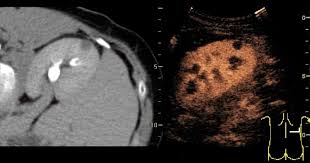

복부 초음파는 초음파(ultrasound)를 이용해 복부 내 장기들의 상태를 확인하는 비침습적 검사 방법입니다. 방사선을 사용하지 않아 인체에 해롭지 않고, 고통 없이 실시간으로 복부 장기들을 관찰할 수 있다는 점에서 가장 기본적이면서도 효과적인 진단도구로 평가받습니다.

초음파 탐촉자(Probe)에서 발생한 고주파 음파가 인체 내부 장기에 부딪혀 반사되며, 복부 초음파로 알 수 있는 것은 바로 이 반사파를 영상화해 간, 담낭, 췌장, 비장, 신장(콩팥), 방광, 대동맥, 림프절 등의 상태를 분석하게 됩니다.